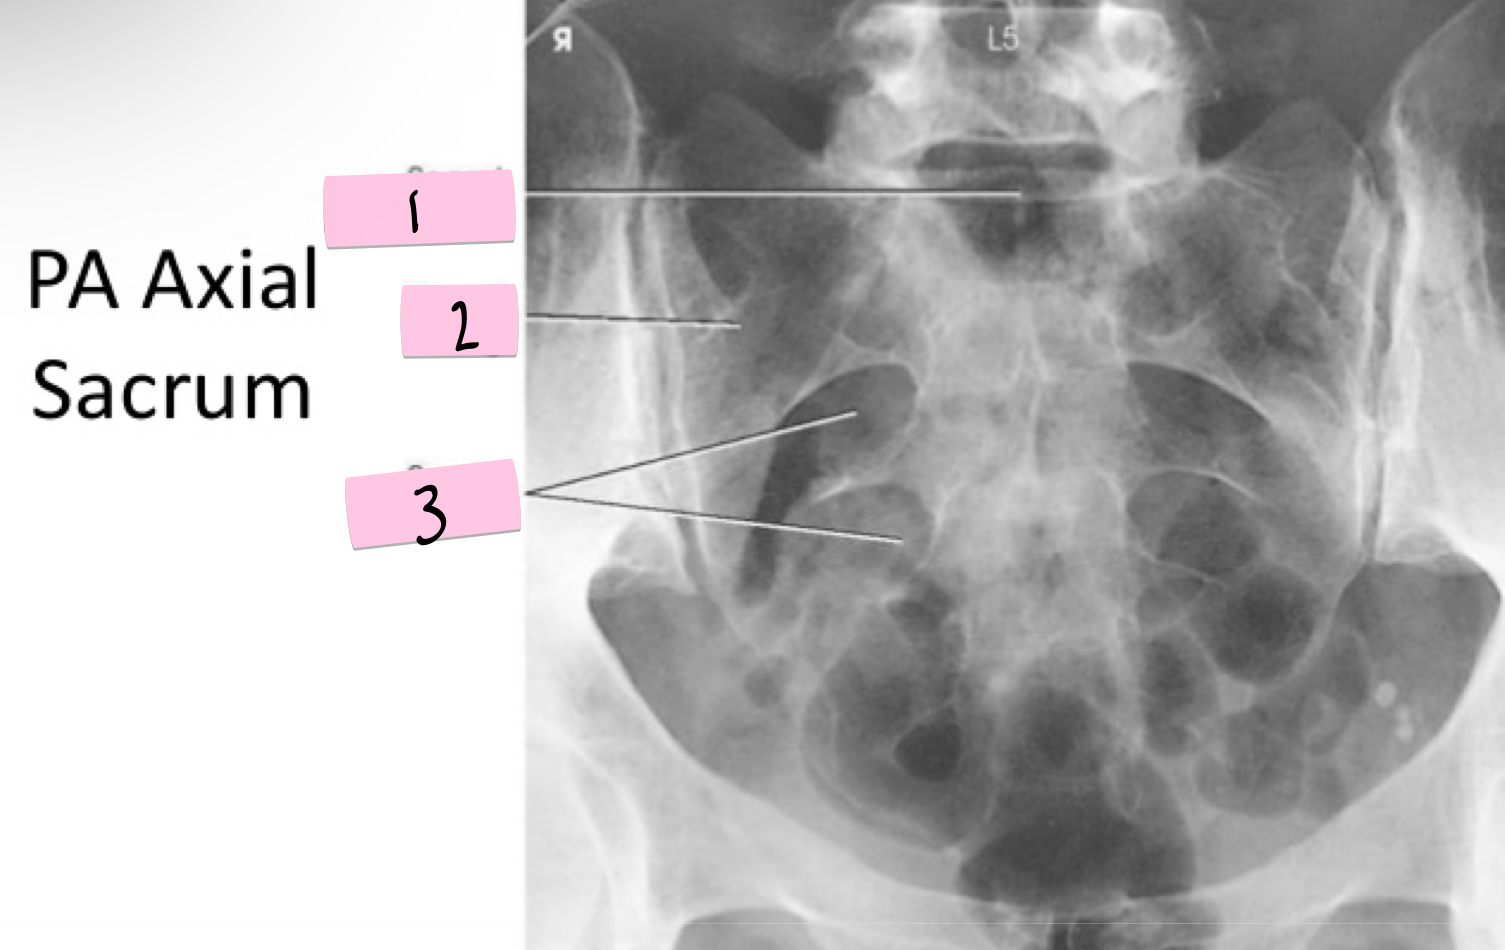

What is 1 pointing to?

Sacral promontory

What is 2 pointing to?

Sacral wing

What is 3 pointing to?

Sacral foramina